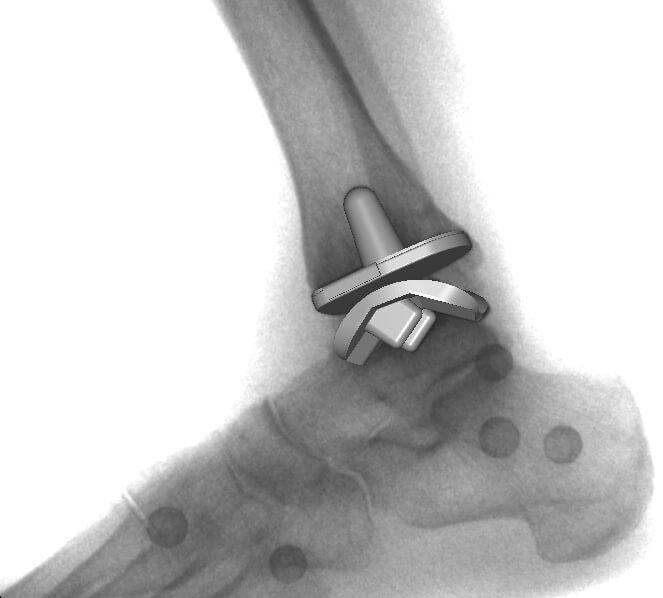

Dans ce propos, nous allons tâcher d’éclairer le lecteur sur la nature des implants utilisés en chirurgie orthopédique pour réaliser les prothèses articulaires (hanche, genou, épaule, coude, cheville, articulations des doigts…). Les termes prothèses articulaires et arthroplasties sont interchangeables même si une nuance puriste peut exister. Le but d’une prothèse articulaire est de remplacer une articulation détruite suite à l’usure liée à l’âge, une infection, une tumeur ou un traumatisme par des implants inertes destinés à restaurer la fonction. On précisera cependant qu’il ne s’agit pas ici de prothèses – appareillages destinées à remplacer un membre amputé.

Actuellement, l’amélioration de la qualité des matériaux ainsi que de leur usinage, surtout le polissage de la surface de friction, ont permis de porter la durée de vie des prothèses au-delà de 30 ans. Trois catégories de matériaux sont actuellement utilisées. Il s’agit des alliages métalliques, des céramiques et du polyéthylène de haute densité. Des essais d’implants en carbone sont en cours.

Les alliages métalliques sont essentiellement en chrome – cobalt et en titane. Les céramiques sont des matériaux non métalliques et non organiques obtenus par l’effet de fortes températures sur de l’alumine ou du zircon. Le polyéthylène est un matériau plastique issu de l’industrie pétrochimique. Il sert à constituer la surface de friction des implants. L’introduction du ciment acrylique dans la fixation des implants à l’os date du début des années 60. Depuis le milieu des années 80, le concept de prothèse sans ciment est apparu. Le principe consiste à recouvrir la surface de contact des implants avec l’os d’un revêtement dit ostéo-conducteur. Il s’agit de l’hydroxyapatite, un composant minéral naturel de l’os que l’on produit artificiellement. Au contact de la prothèse, l’os du voisinage identifie cet hydroxyapatite comme un de ses propres constituants et le colonise. La prothèse devient ainsi intégrée à l’os. On parle alors de stabilité secondaire. Naturellement, en attendant cette repousse d’os sur le revêtement d’hydroxyapatite, la stabilité primaire est assurée par l’impaction en force de la prothèse dans l’os et éventuellement fixée par des vis complémentaires. Les couples de friction (surface de frottement des implants) sont de plusieurs sortes : métal – PE, céramique – PE, céramique – céramique. Le couple métal – métal dit de gros diamètre a été utilisé au moins durant trois périodes depuis le 20ème siècle dont la dernière au-début des années 2000 avant d’être à nouveau abandonné pour cause de relargage excessif de particules de métal dans l’organisme.